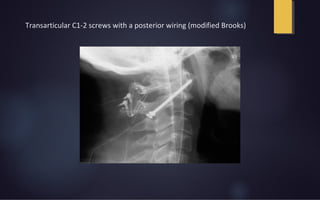

Transarticular C1-2 screws with a posterior wiring (modified Brooks)

Transarticular Screws • Increasedrotational stability • Not require stable posterior arch • High fusion rate; immediate stabilization • Risk of injury to vertebral arteries

Transarticular C1-2 screwswith a posterior wiring (modified Brooks)